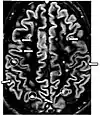

| Fluid-attenuated inversion recovery | FLAIR | Fluid suppression by setting an inversion time that nulls fluids | High signal in lacunar infarction, multiple sclerosis (MS) plaques, subarachnoid haemorrhage and meningitis (pictured).[76] | ![]() | |